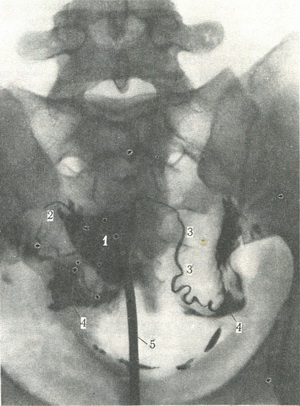

Тінь порожнини матки має трикутну форму (рис. 334). Якщо маткові труби прохідні, то від підстави трикутника починається внутристеночная звужена частина труби, потім вона, розширюючись в перешийку, переходить в ампулу. Контрастна речовина потрапляє в очеревину порожнину. На знімках матки можна встановити деформацію маткової порожнини, прохідність труб, наявність дворогій матки та ін

334. Гисгеросальпингограмма - знімок контрастованих порожнин матки і труб (по Л. Д. Линденбратену). 1 - порожнина матки; 2 - права маткова труба; 3 - ліва маткова труба; 4 - скупчення контрастної речовини в очеревинної порожнини; 5 - катетер, введений в матку.  |